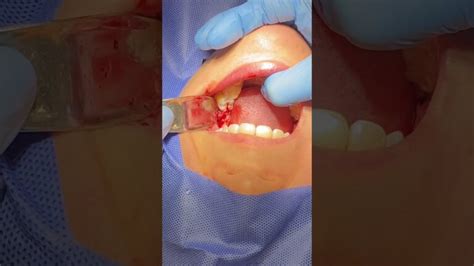

- Extracción quirúrgica: La cirugía de extracción de muela del juicio se lleva a cabo cuando está retenida o parcialmente erupcionada. Durante la operación, el cirujano debe hacer una incisión en la encía para acceder al diente (a veces dividiéndolo en secciones para facilitar su extracción).

Una vez que la anestesia hace efecto, el cirujano oral, con ayuda de instrumentos específicos, procede a extraer la muela, ya sea entera o fragmentada en piezas más pequeñas para simplificar la extracción.

En la mayoría de los casos, este procedimiento es bastante directo y se completa en solo unos minutos. Aún así, cabe señalar que, dependiendo de cómo esté posicionada la muela, el proceso de extracción puede ser diferente.